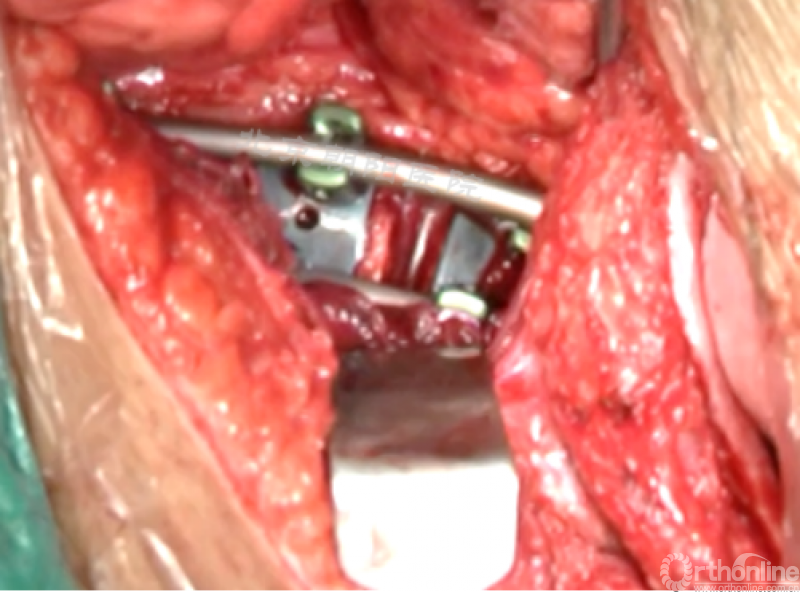

内固定选择的是5.5mm双棒系统,先置入顶椎的螺钉垫板。

置入顶椎的椎体螺钉,螺钉可置入椎体中部到后方1/3之间的范围内。

使用双棒系统时,先置入背侧的螺钉,螺钉指向椎体中线,后置入腹侧的螺钉,螺钉轻度指向后侧。形成对椎体的三角形抓持力。

胸腔侧、腹腔侧螺钉全部置入后,骨移植物植人的越靠近后纵韧带或者纤维环的后缘越好。

将预先折弯的金属棒先置入背侧。

椎间融合器经前方置入凹侧,确保腰椎前凸的恢复和冠状面畸形的矫正,将剩下的骨移植物置入椎间隙内。

置入腹侧金属棒。

使用双棒系统时先安装背侧的棒,可进行90°的去旋转,也可以直接通过前方螺钉矫正冠状面和矢状面的畸形,然后固定后方的棒,可进一步通过加压矫正冠状面畸形。

矫正后神经检测未见异常术中唤醒患者下肢活动良好,术中透视矫正效果满意、内固定位置良好。根据手术具体情况放置合适尺寸的横连接加强内固定。